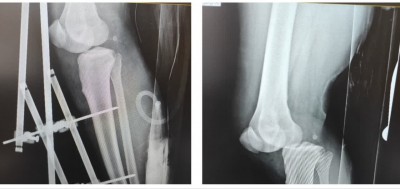

بیمار آقای ۳۱ ساله که بدنبال سقوط از ارتفاع دچار در رفتگی خلفی زانو راست شده بود

که پس از پذیرش در بیمارستان و تشخیص بموقع پزشک محترم اورژانس و اطلاع به

سرویس ارتوپدی بیمار در کمتر از 30 دقیقه به اتاق عمل منتقل شده.تحت جا اندازی

و تعبیه اکسترنال فیکساتور و بازگشت نبض قرار گرفت. خوشبختانه عمل با موفقیت انجام شد